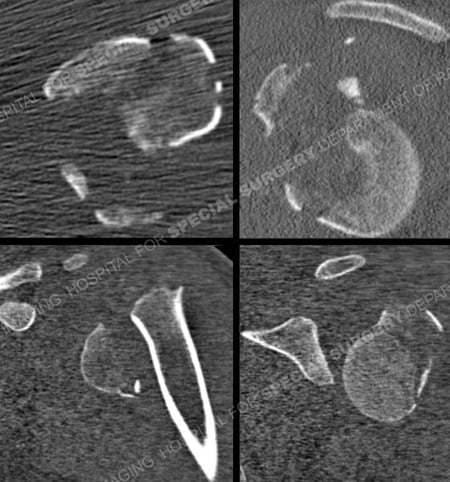

CT Scans revelaing proximal humerus fracture from a case example of should fracture from the orthopedic trauma service at Hospital for Special Surgery.

CT scan images further delineating the fracture pattern and medial comminution.